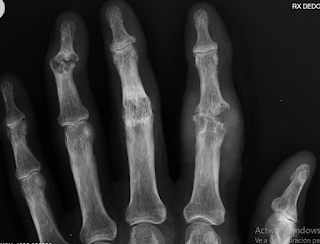

Las lesiones óseas de las manos son un tipo de daño que afecta a los huesos de la mano. Pueden ser causadas por una variedad de factores, como accidentes, caídas, golpes o movimientos repetitivos.

Los tipos más comunes de lesiones óseas de las manos son:

Fracturas: Una fractura es una rotura en el hueso. Las fracturas de las manos pueden ser causadas por un golpe directo, una caída o un movimiento repetitivo.

Luxaciones: Una luxación es una dislocación de una articulación. Las luxaciones de las manos pueden ser causadas por un golpe directo o un movimiento repentino.

Artritis (inflamatoria o degenerativa): Esto pueden ser causadas por un movimiento repetitivo y un esfuerzo excesivo o por causas inflamatorias o familiares de diferente índole.

![]() |